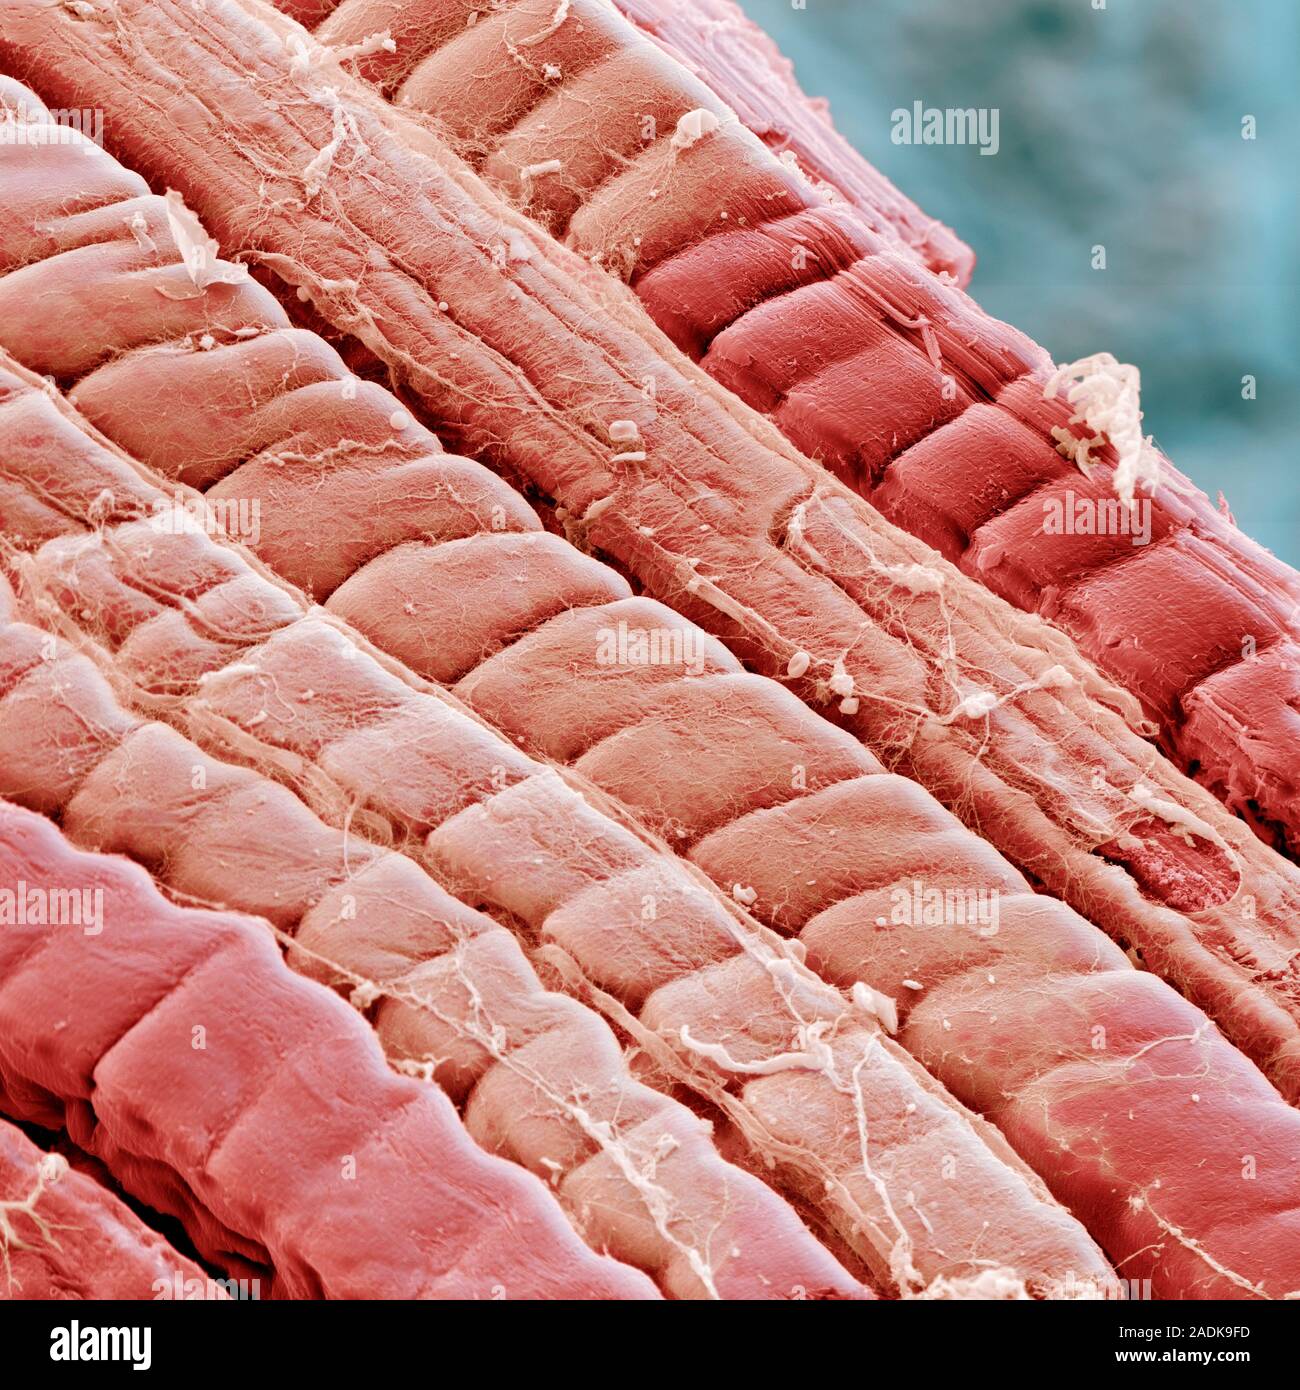

Молочная кислота в мышцах - это обычное явление, которое происходит в результате физических нагрузок. Она образуется в мышцах во время интенсивных тренировок, когда организм не может обеспечить достаточное количество кислорода для процесса окисления глюкозы. Это приводит к накоплению молочной кислоты в мышцах, что может вызвать ощущение жжения и усталости.

Молочная кислота может вызвать ощущение усталости и дискомфорта в мышцах во время и после тренировки. Однако, это является естественной реакцией организма на интенсивные нагрузки. Со временем мышцы адаптируются к процессу накопления молочной кислоты, что позволяет улучшить выносливость и способствует росту мышечной массы.